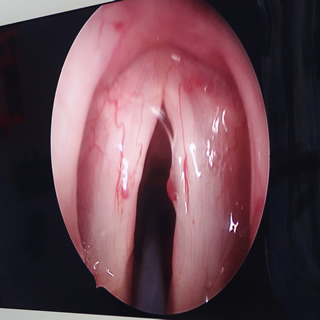

Videolaringoscopía: Dispositivos utilizados en el manejo de la vía aérea desde más o menos el año 2004, especialmente en casos de intubación difícil; también son de mucha utilidad para la docencia ya que permite a los observadores aprender esta técnica con mayor facilidad que la laringoscopía tradicional. Desde el año 2013 fueron incorporados al algoritmo de manejo de la vía aérea de la Sociedad Americana de Anestesiología (ASA). Este taller mostrará una amplia variedad de videolaringoscopios y cómo usarlos en la intubación endotraqueal.